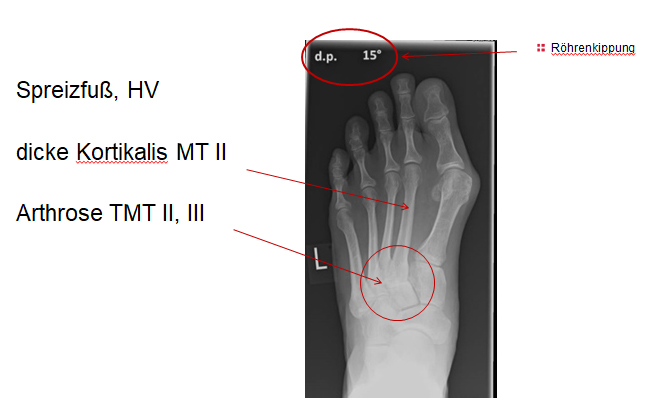

Die Überbelastung im Schaftbereich wird selten von den Patienten wahrgenommen. Manchmal findet sich vor allem am Os metatarsale II proximal eine Stressfraktur. Adaptiert sich der Knochen, kann im Röntgenbild häufig eine Kortikalisverdickung im Bereich der Metatarsale II und III Schäfte als Ausdruck einer vermehrten Lasteinleitung beobachtet werden (Abb. 4).

Zum Lesen der Bildbeschreibung und zur Vollansicht bitte das Bild anklicken. Bild: C. Hase.

Eine Röntgenaufnahme unter Belastung mit Abbildungen des ganzen Fußes a. p. (mit 15-20° Röhrenkippung) und seitlich, sowie Schrägaufnahmen, reichen meist zur Diagnose. Manchmal ist ein MRT und DVT ergänzend hilfreich. Selten wird die Indikation für ein SPECT CT gestellt (Abb. 6).